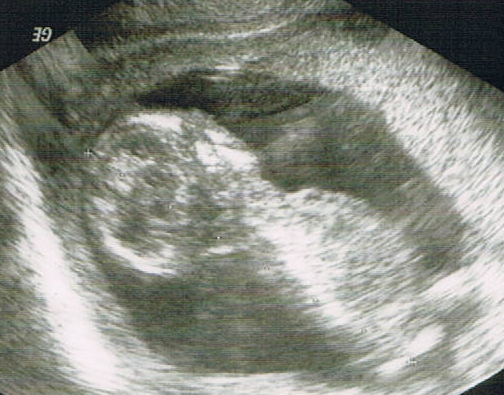

Ultraschallbild (Velen)

„Dann gucken wir uns den Wurm doch mal an“, schlägt sie ein wenig später vor. Während ich meinen Unterkörper in einer separaten Vorkehrung mit großen Vorhängen entkleiden kann, quatsche ich sie beim Ausziehen durch den Vorhang zu und begebe mich dann auf die Liege.

Ultraschall – jedes Mal schlägt mein Herz höher. Plötzlich kriege ich eine Gänsehaut. Es scheint so, als würde mein Baby mir zuwinken. Dann betrachten wir das Seitenprofil. Wow – das Köpfchen ist ja gut zu erkennen.